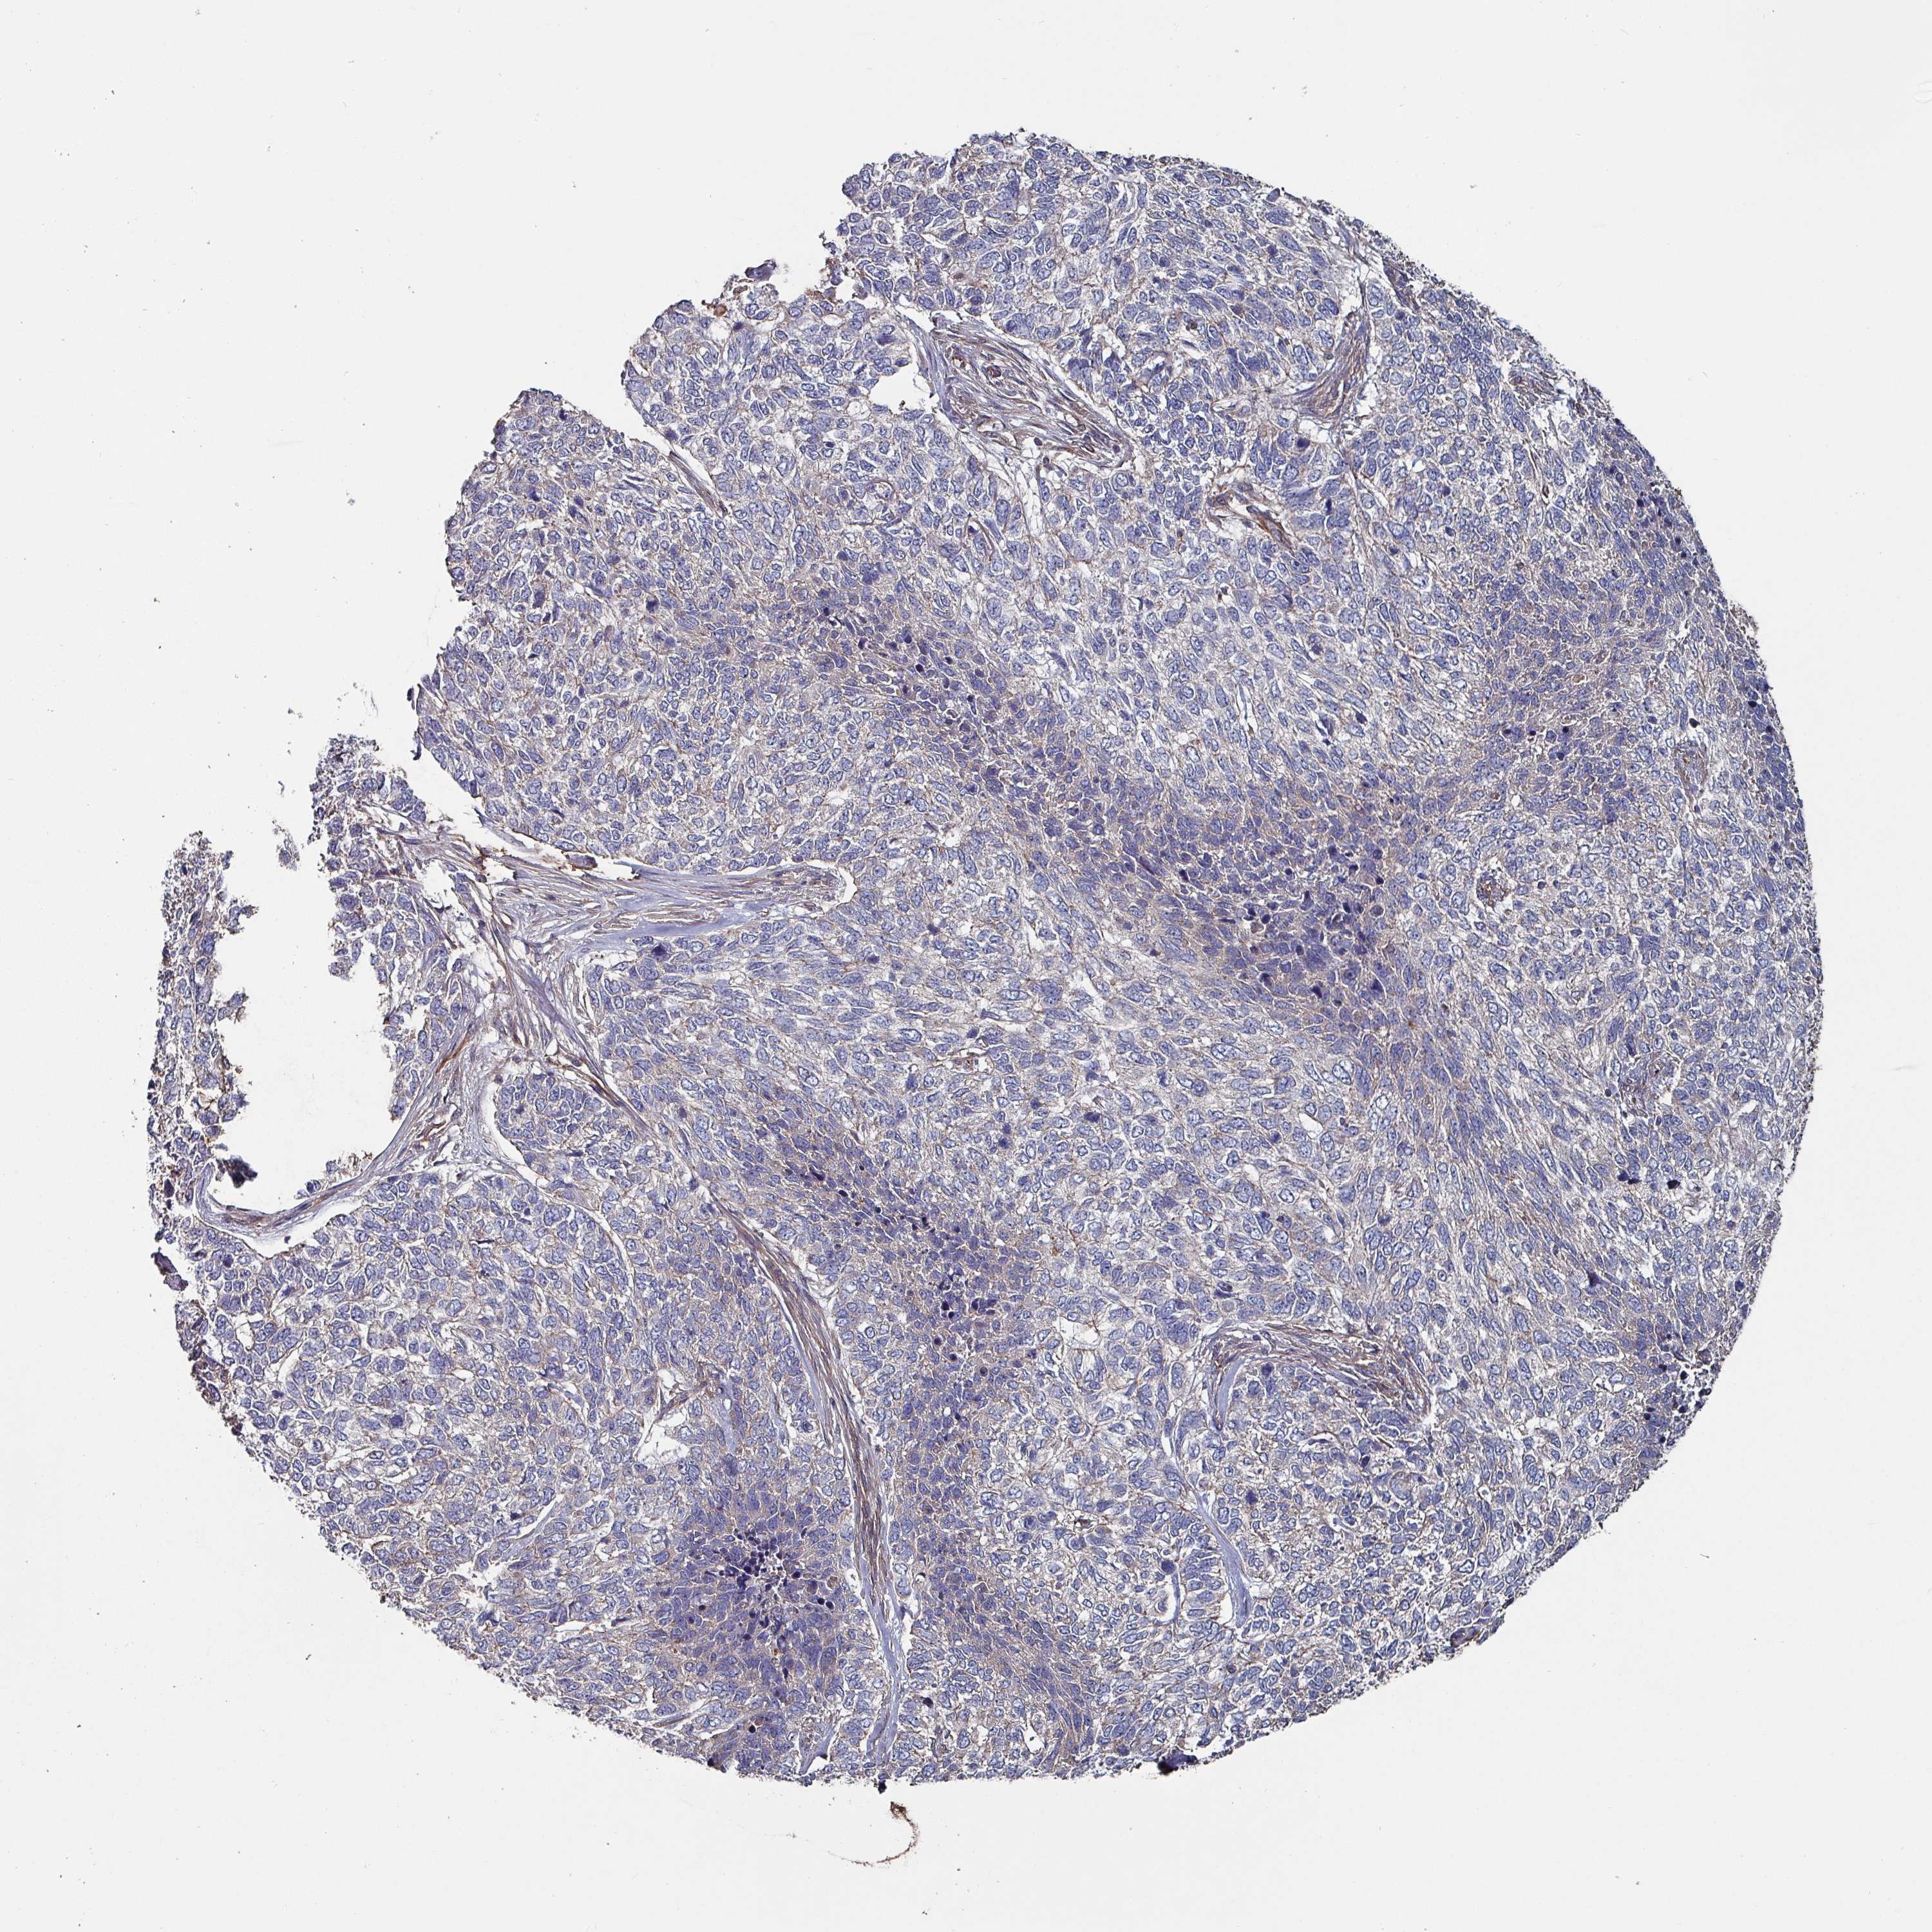

Basal cell and squamous cell cancer

SKIN CANCER - Protein expressioni

A mouse-over function shows sample information and annotation data. Click on an image to view it in a full screen mode. Samples can be filtered based on level of antibody staining by selecting one or several of the following categories: high, medium, low and not detected. The assay and annotation is described here.

Antibody stainingi

Antibody staining in the annotated cell types in the current human tissue is reported as not detected, low, medium, or high, based on conventional immunohistochemistry profiling in selected tissues. This score is based on the combination of the staining intensity and fraction of stained cells.

Each image is clickable and will lead to virtual microscopy that enables deeper exploration of all samples and also displays staining intensity scores, fraction scores and subcellular localization as well as patient and tissue information for each sample.

Antibody HPA051569

Staining

High

Medium

Low

Not detected

Intensity

Strong

Moderate

Weak

Negative

Quantity

>75%

75%-25%

<25%

None

Location

Nuclear

Cytoplasmic/membranous

Cytoplasmic/membranous,nuclear

Basal cell carcinoma